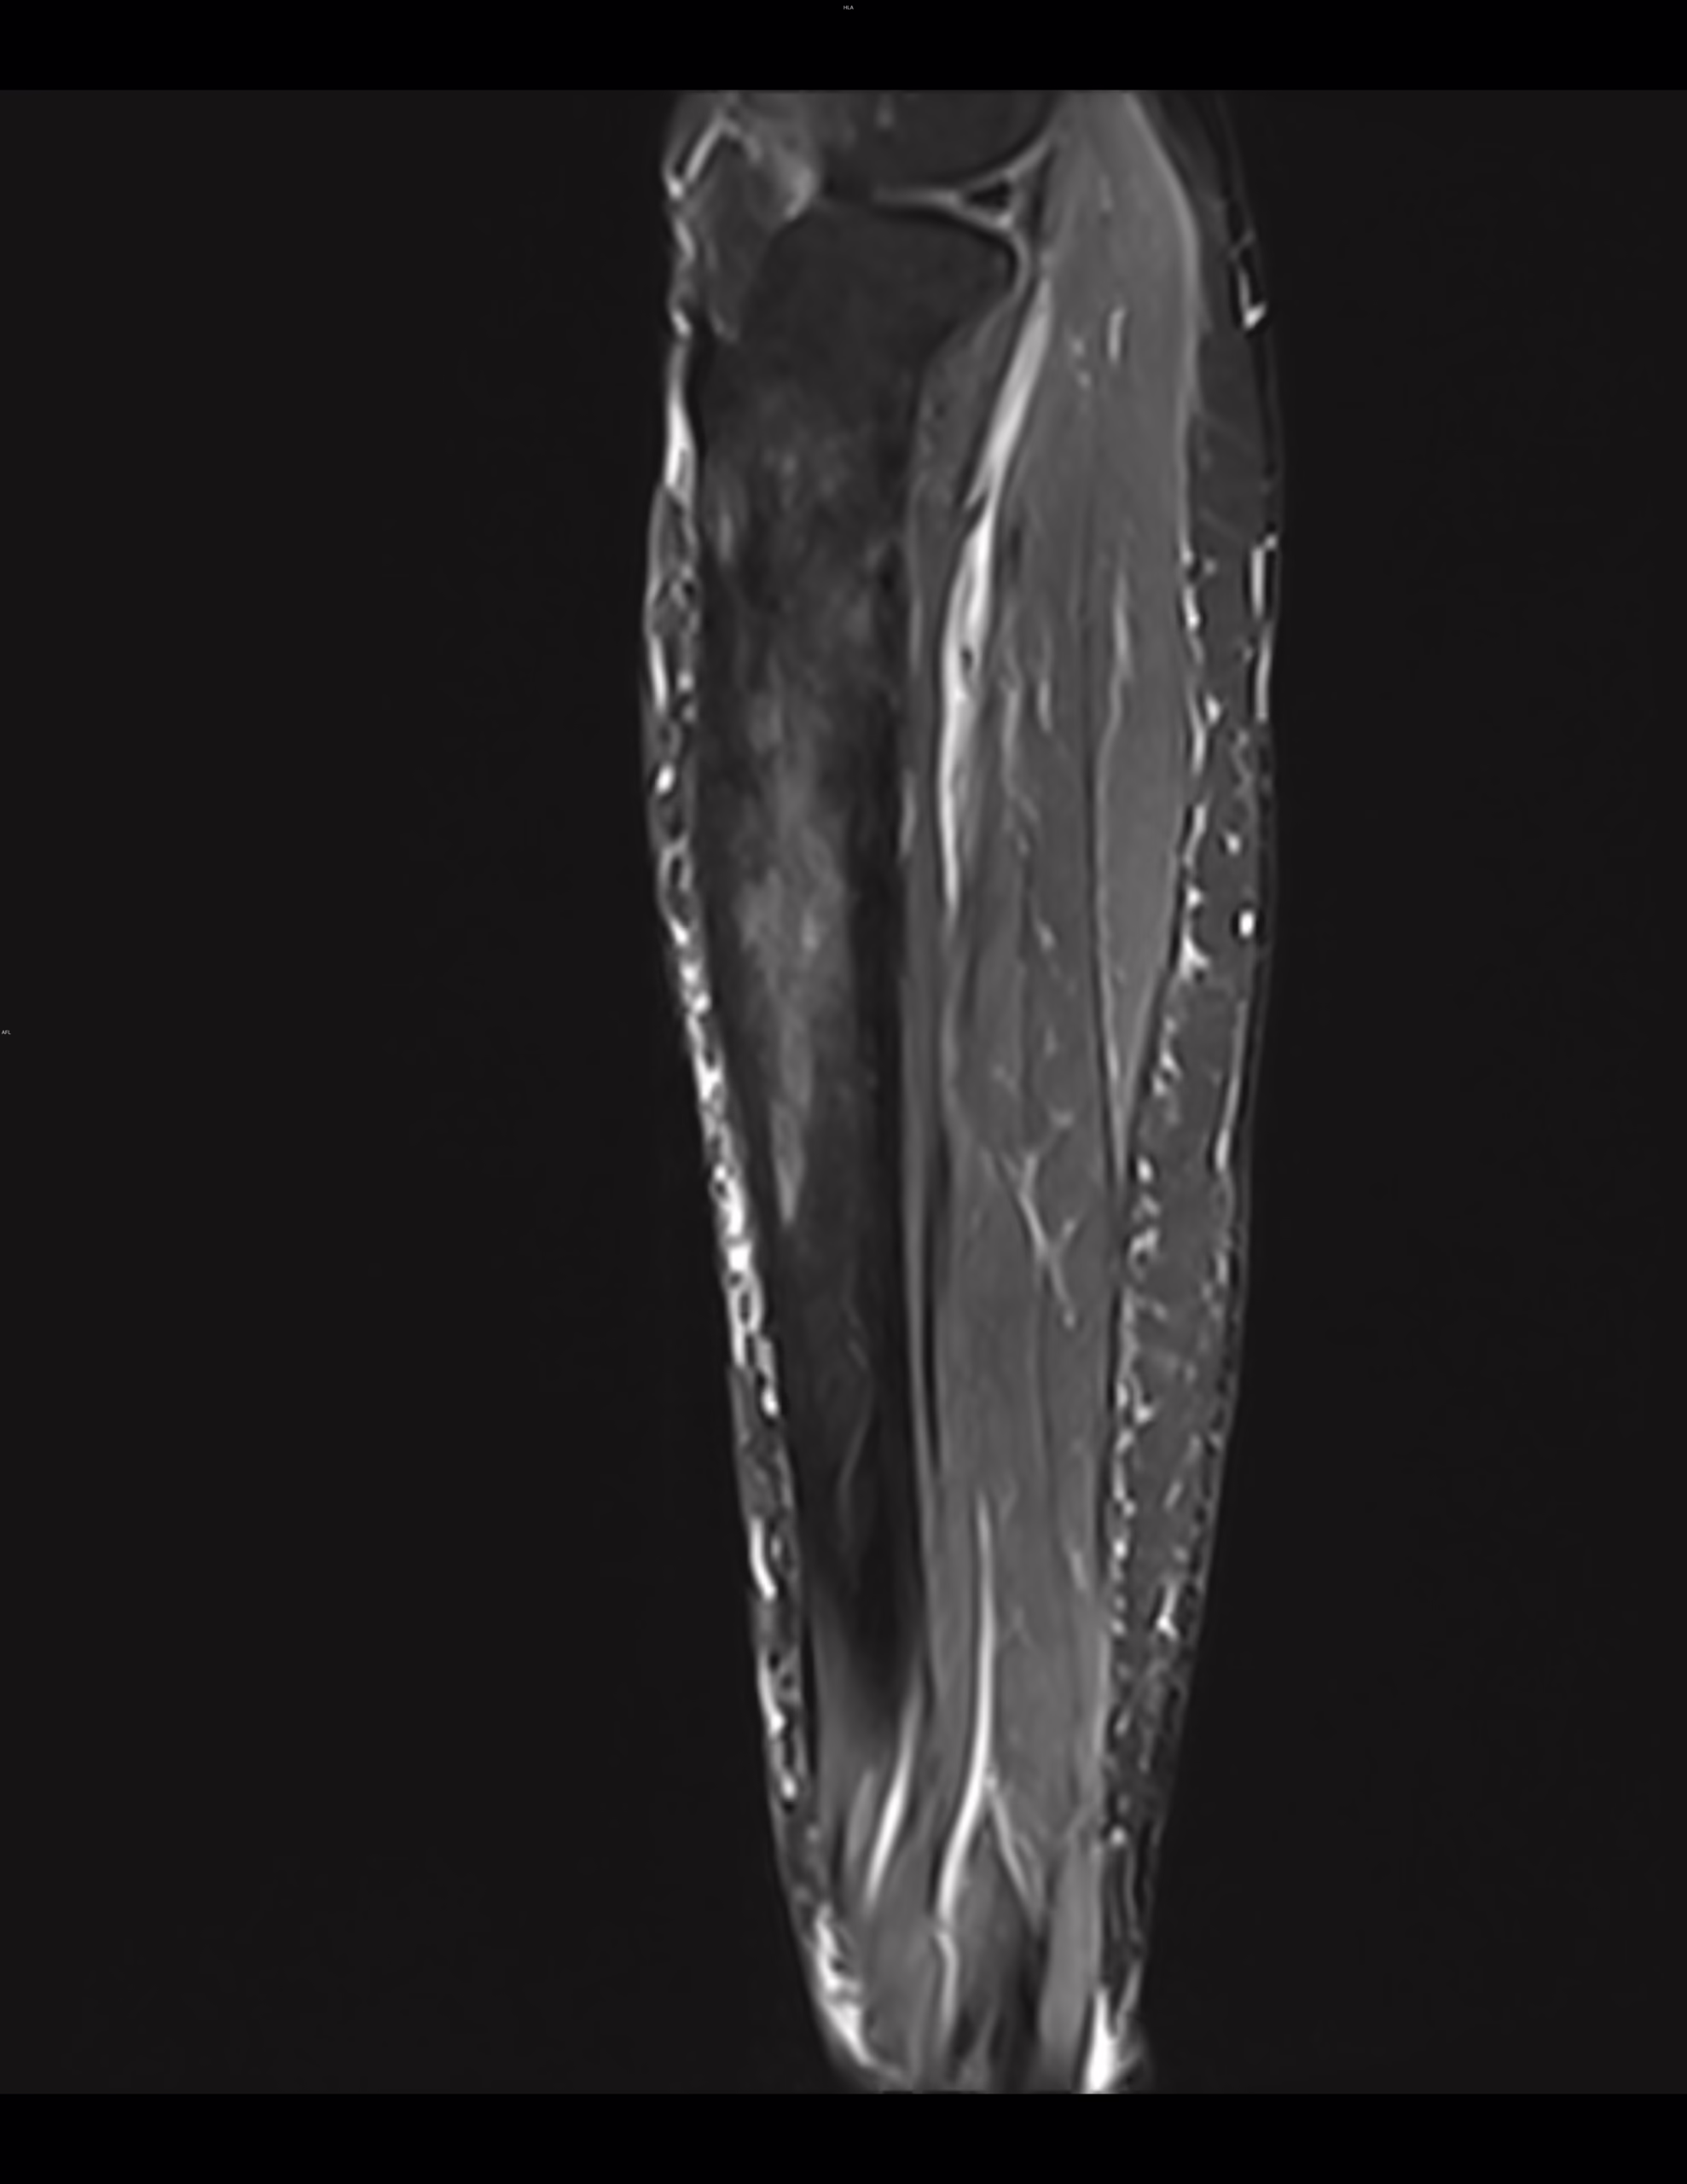

rnm

Se realizaron cortes sagitales, axiales y coronales con técnica de espín eco con el protocolo habitual.

Se identifican edema en el tejido celular subcutáneo adyacente a la tibia y grupos musculares en la región anterior y medial de la pierna.

Existen cambios en la morfología e intensidad del hueso esponjoso de la tibia que involucra la diáfisis proximal y tercio medio con áreas de baja intensidad en el hueso esponjoso medular así como de mayor intensidad, la cortical al parecer se encuentra conservada.

La intensidad de las estructuras musculares se encuentra conservada.

IMPRESION DIAGNOSTICA:

Edema en el tejido celular subcutáneo adyacente a la tibia y grupos musculares en la región anterior y medial de la pierna.

Existen cambios en la morfología e intensidad del hueso esponjoso de la tibia que involucra la diáfisis proximal y tercio medio con áreas de baja intensidad en el hueso esponjoso medular así como de mayor intensidad, la cortical al parecer se encuentra conservada, cambios de proceso infiltrativo óseo de etiología a determinar.